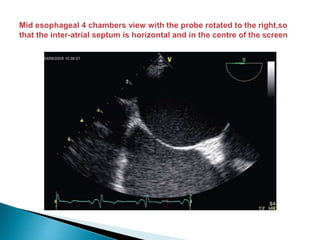

 From the mid esophageal 4 chambers view the probe is rotated to the right (with the

image sector angle at 0–30° and depth at about 10 cm) such that the inter-atrial septum is

horizontal and in the centre of the screen .